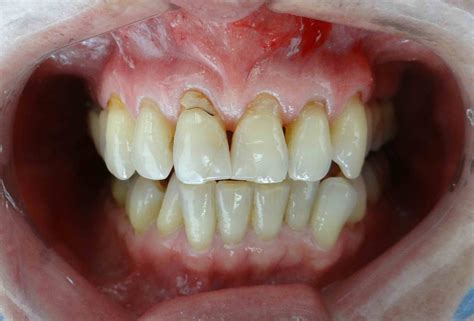

Cuando hablamos de encías retraídas nos referimos a un desplazamiento del tejido gingival que provoca una sobreexposición del diente. Las encías se desplazan hacia arriba en los dientes superiores y hacia abajo en los dientes inferiores dejando al descubierto parte de la raíz dental. Esto no solo afecta a la estética, sino que también compromete la protección natural de los dientes, aumentando la sensibilidad y el riesgo de enfermedades.

Hablamos de encías retraídas cuando el tejido gingival que rodea tu diente se desplaza en sentido apical, dejando al descubierto parte de la raíz dentaria. La superficie radicular está recubierta por un tejido llamado cemento, que no está preparado para estar en contacto con el exterior. Asimismo, si tienes pérdida de tu encía, el cepillado dental puede volverse dificultoso por la sensibilidad. Esto favorece el acúmulo de placa bacteriana y la formación de sarro, situaciones que irritan tu tejido gingival e incrementan la retracción.

- Color diferente en la línea de encías: Si eres un poco observador puedes detectar tonos distintos entre la raíz expuesta y la corona del diente.